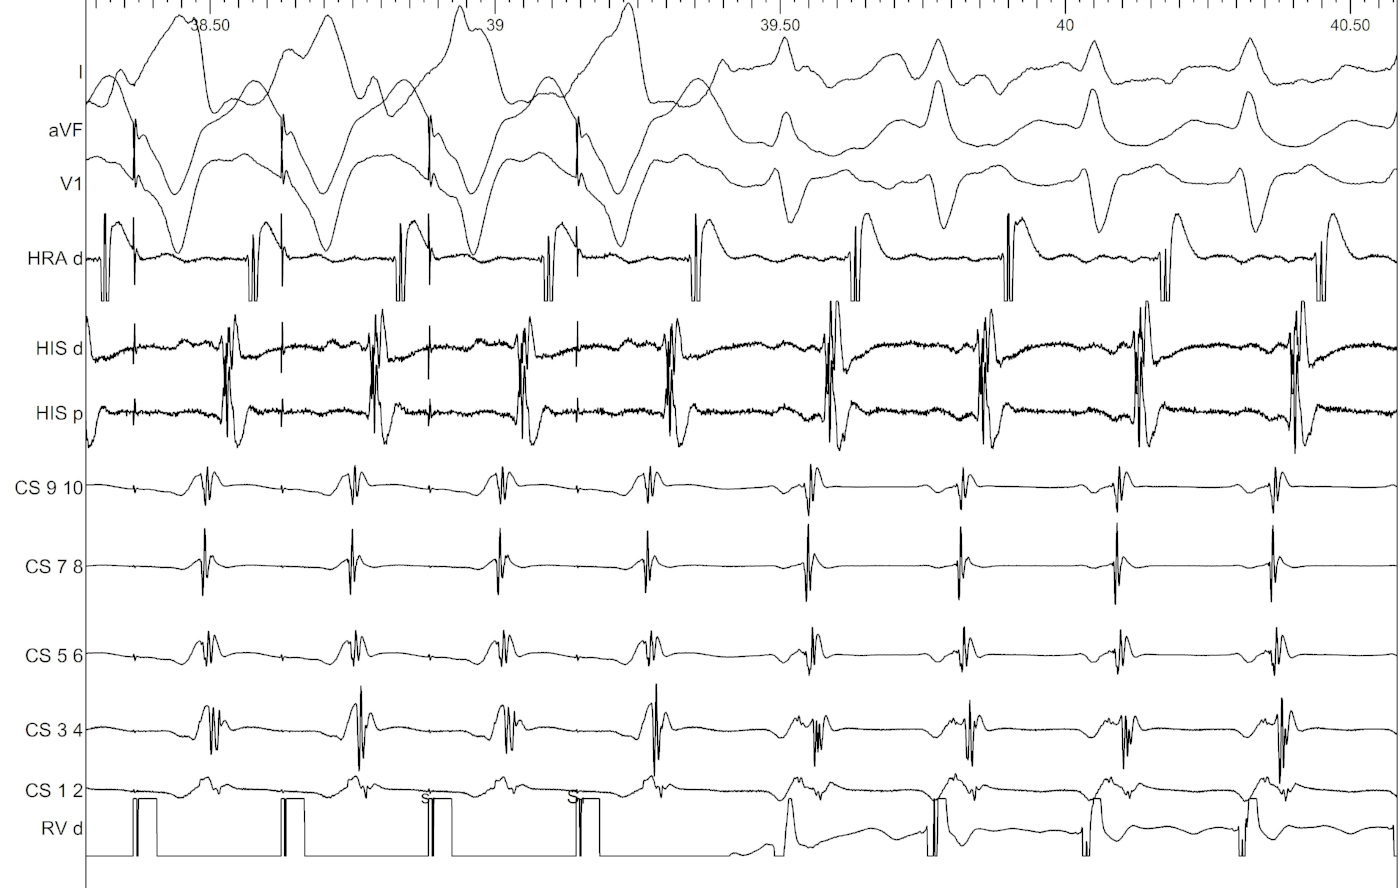

Ventricular overdrive pacing

vop_eccentric.jpg

Response to VOP

• Unable to entrain - AT

• Identical atrial activation, VAV - AVRT

• Different atrial activation, VAAV / failure of atrial capture - AT